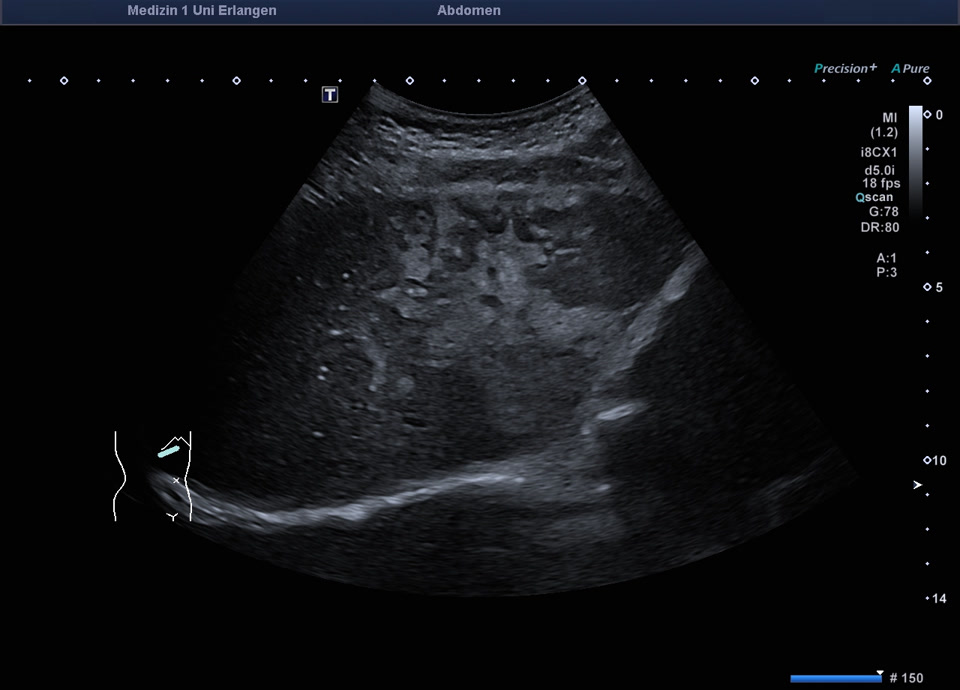

Lobuläre Mehrverfettung des rechten Leberlappens (siehe auch nächstes Bild)

Lobuläre Mehrverfettung des rechten Leberlappens